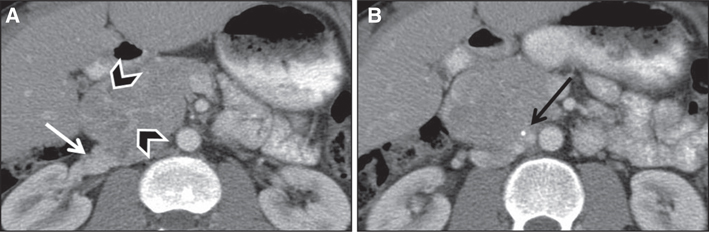

With contrast administration, PPGLs tend to enhance rapidly and avidly due to a rich capillary network (Figures 3 and 4). Adrenal adenomas usually demonstrate milder enhancement than pheochromocytomas or malignant tumors but have faster washout. Absolute washout of more than 60% or relative washout of more than 40% has been previously accepted as being characteristic of benign adrenal adenoma, although more recent studies have suggested that a good proportion of pheochromocytomas, potentially up to one-third, can have washout characteristics similar to benign adenomas (20, 21).

Fig 3

Figure 3 Pheochromocytoma in a 39-year-old male patient with neurofibromatosis type 1. (A) Noncontrast images demonstrate a hypodense lesion in the right adrenal gland (arrowheads), with (B) marked enhancement after contrast administration. (C) Adrenal washout phase acquired 15 min after contrast administration demonstrates rapid washout, which is usually seen with adrenal adenomas but can be seen in one-third of pheochromocytomas. The patient had elevated metanephrines, and surgical pathology was consistent with pheochromocytoma.

Fig 4

Figure 4 Paraganglioma in a 30-year-old male patient. Images obtained after administration of iodinated intravenous contrast demonstrate heterogeneously hyperenhancing retroperitoneal mass compressing the right renal vein (white arrow) with prominent vascular feeders (arrowheads) and a peripheral calcification (black arrow).